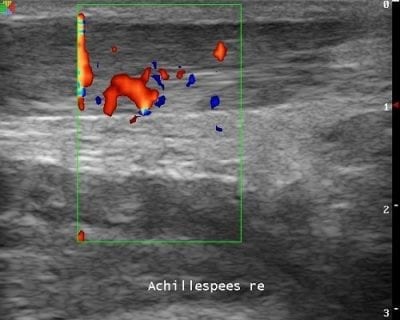

Het gebruik van echografie, ook wel musculoskeletal ultrasound (MSU), is binnen de podotherapie vrij nieuw. Met een behandelkop, de zogenaamde ‘transducer’, worden hoogfrequente geluidsgolven in het lichaam gestuurd en weer opgevangen. De teruggezonden geluidsgolven worden omgezet in een beeld met grijstinten.

Podotherapie Reggestreek heeft de beschikking over een eigen echografieapparatuur van de merken Philips en Ultrasonix met kleurendoppler waarmee ontstekingen gezien kunnen worden. Ons apparatuur krijgt elk jaar een onderhoudsbeurt en veiligheidstest.